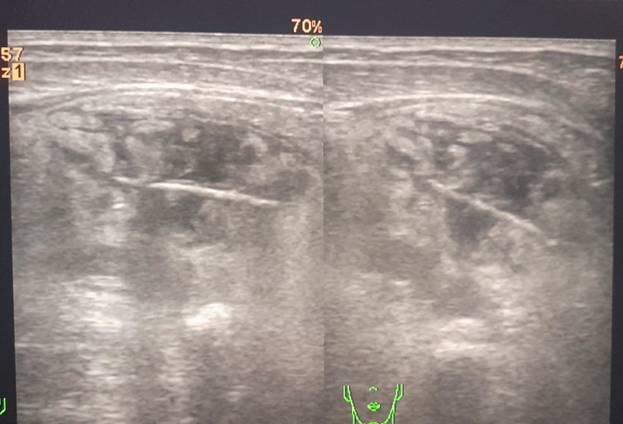

Hình ảnh viêm phúc mạc do dị vật( tăm tre) xuyên thành ruột

được phát hiện qua siêu âm (Bs Lê Thị Liễu cung cấp)

Được biết, người bệnh thường có thói quen ngậm tăm trong miệng sau khi ăn, thậm chí ngậm tăm khi đi ngủ. Người bệnh nhập viện trong tình trạng đau bụng đột ngột, dữ dội vùng thượng vị, sau đau lan ra khắp ổ bụng. Qua kết quả thăm khám lâm sàng, chụp X-Q, siêu âm phát hiện hình ảnh dị vật dài 30mm( nghĩ đến tăm tre), thành ruột quanh vị trí dị vật dày, xung quanh có thâm nhiễm mỡ diện rộng (nghĩ đến viêm phúc mạc).